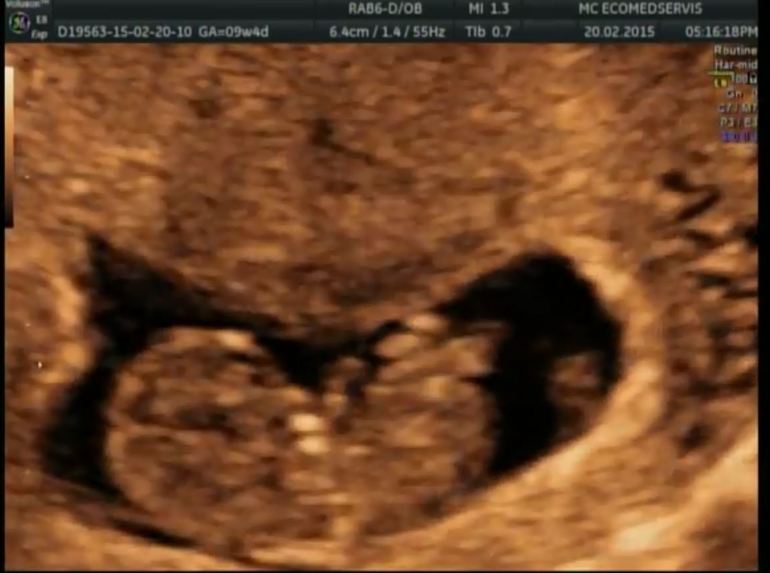

УЗИ, КТГ, доплерНа неделе встала на учет, На первый скрининг записали во второй роддом 9 марта. А вчера ходила на узи... Я наконец-то поняла, что стану мамой! Ещё пару месяцев назад там была только маленькая точечка, а теперь там человечек!!!! С ручками и ножками! Он так смешно ими шевелит! В общем, я там чуть не расплакалась...

С детёнышем все хорошо, развивается нормально, отслойки больше нет.

Послушали сердечко, записали все на диск для мужа )))